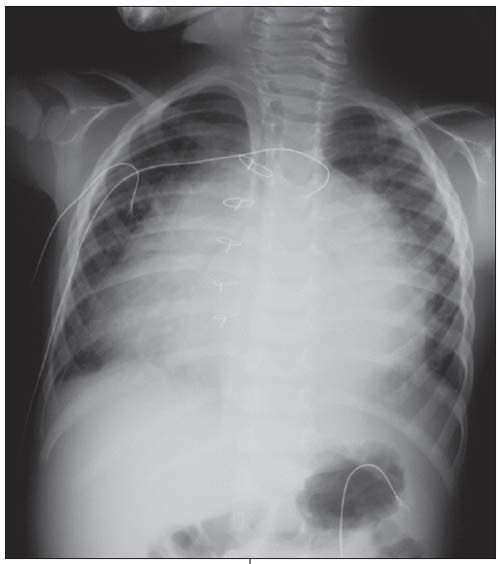

Chest radiograph is shown.

Postpericardiotomy syndrome is the development of pericarditis or symptomatic pericardial effusion a few days or weeks after a cardiac operation; atrial septal defect (ASD) repair is a common cause. The chest radiograph shows massive enlargement of the heart in a globular shape, indicative of a large pericardial effusion. In one series of 87 children who underwent surgical closure of an ASD, postpericardiotomy syndrome developed in 6%.1 This syndrome is thought to be an inflammatory or immune-mediated process. Viral infections may serve as a triggering event, although none have been specifically implicated.2

A chest radiograph can be suggestive of the diagnosis-as in this patient-especially when the clinical suspicion is high. An ECG can also be helpful. Generalized suppressed voltage is the most common finding. Occasionally, you may also see electrical alternans-beat-to-beat variability in voltage produced by the swinging of the heart in the pericardial fluid.4 An echocardiogram is most specific and can help delineate the degree of effusion. When clinical suspicion is high, diagnostic testing should not delay definitive treatment.